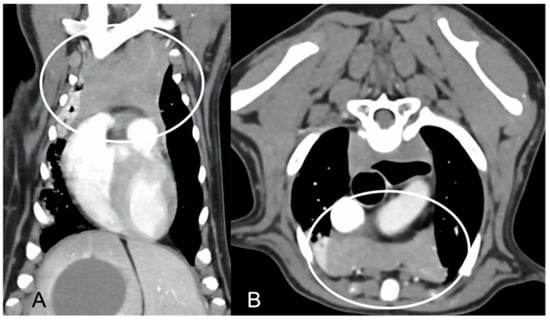

In both groups, most of the dogs presented with a triangular thymus (Figure 1); in the adult group, some dogs had an elongated thymus, and in the juvenile group, some dogs had a flattened thymus (Figure 2).

Figure 1. Shape of the thymus (circled) in an adult dog (A) compared to a young dog (B). Post-contrast dorsal CT reconstruction. Note the different relative sizes of the thymus in the two dogs, and the heterogeneous (lobulated) appearance of the thymus in (A) with respect to the thymus in (B). In both cases, the shape of the thymus is triangular.